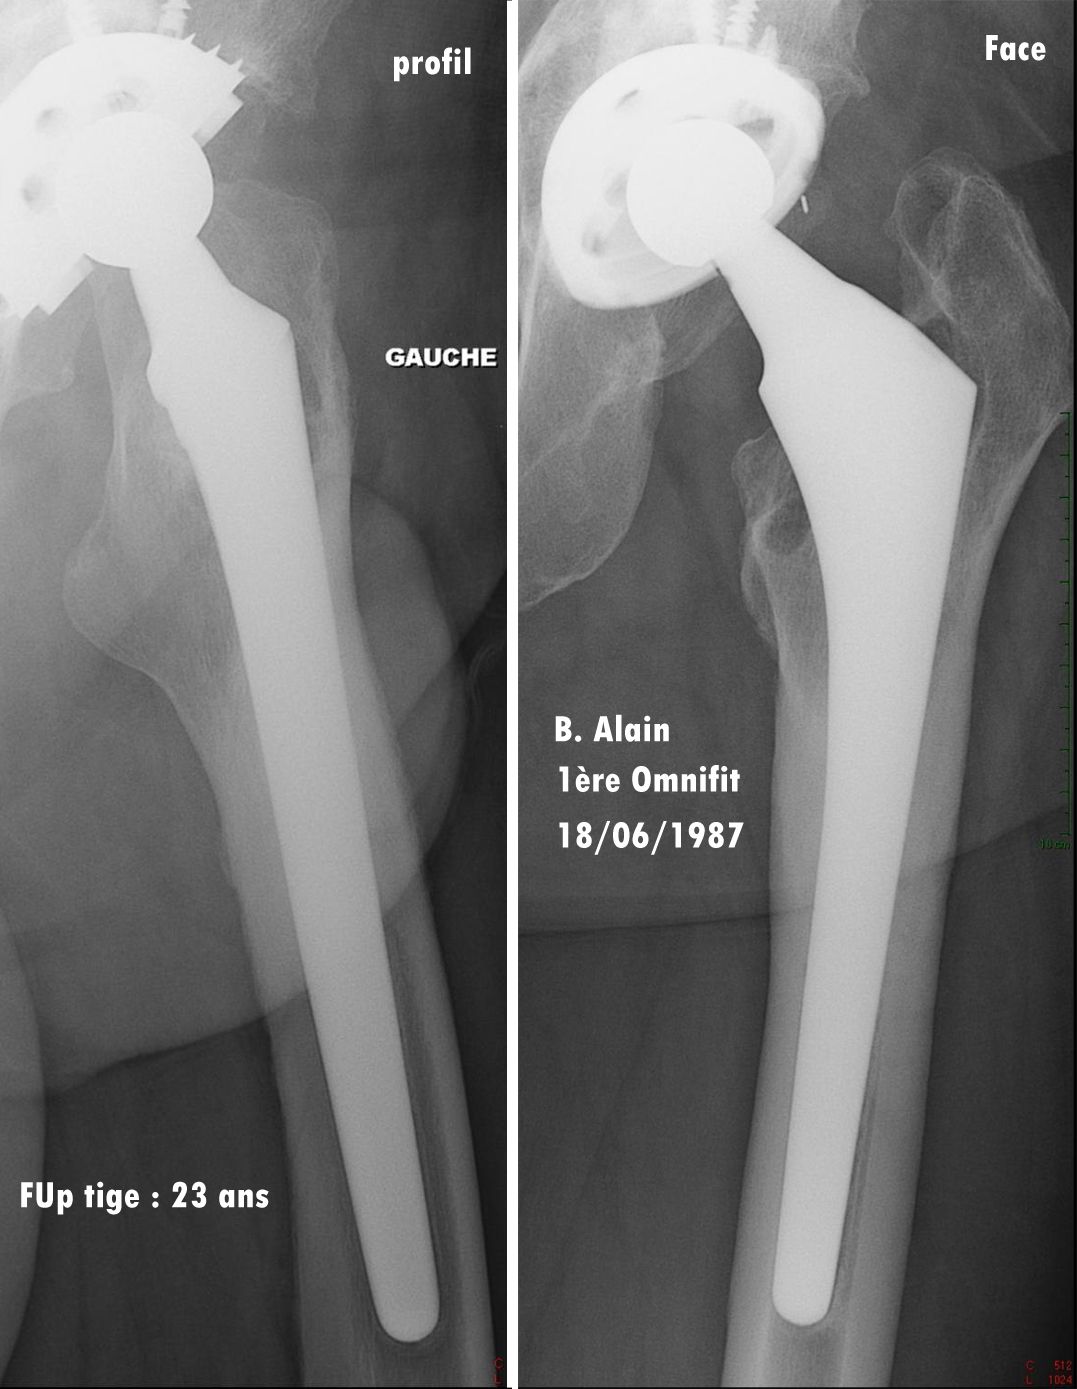

The minimum follow-up for the study was 20 years, and it encompasses two families of proximally HA-coated stems, first the Omnifit HA, which was used between 1987 and 2000, followed by the ABG II from 2001 onwards. Both models are made from titanium alloy coated with a thin layer of hydroxyapatite (60 microns) on their proximal third to provide a ‘metaphyseal-engaging’ design. As counterpart to the stem, the acetabular component used until 2007 was the Arc 2F HA-coated screwed cup comprising a standard PE insert until 1998 then a ceramic-on-ceramic cup in 1999 and 2000, replaced with a highly crosslinked PE insert in 2001.

Overall, these proximally HA-coated stems demonstrated excellent osteoapposition, optimal radiological fixation with bone growth in all cases, and no deterioration in outcomes even after 20 years. (Figs. 3, 4 & 5).

Whatever the timescale, these proximally HA-coated stems produced excellent results, even in this ‘high-risk’ population, and the outcomes were long-lasting, with no deterioration over the years, even in the very long-term after 2–3 decades. These excellent clinical outcomes are corroborated by the radiological study, which confirms bone growth in all cases for the two types of stem studied, confirming previous publications [10] and without any deterioration over time.